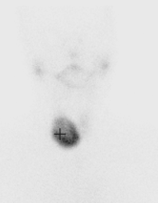

A 30yo patient presents to the ED in hypertensive crisis. They also complain of a headache and palpitations. The patient’s partner noted they have had a few similar episodes to this in the past involving headache, palpitations, sweating and pallor

Phaeochromocytoma